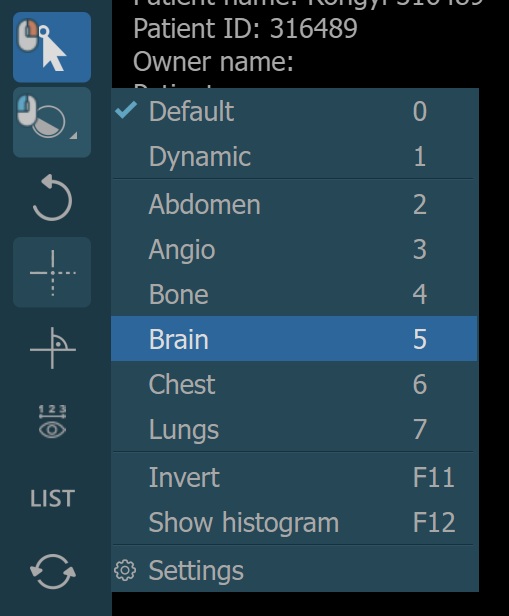

There are two different windowing modes available in the CT Viewer, Default and Dynamic. Change the active windowing mode by using the menu when selecting the Windowing tool.

The windowing presets are also available from the windowing menu when the default windowing mode is active.

Dynamic Windowing¶

The preset values for the dynamic windowing mode are represented as a percentage of the maximum determined windowing range. All of the preset values are available in the windowing menu when dynamic mode is active.